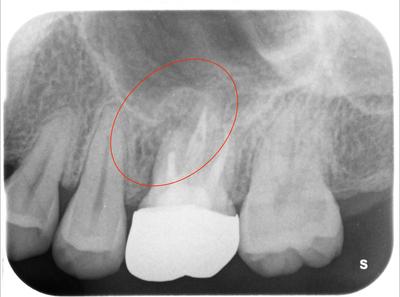

補綴物除去し、確認したところ、未処置のMB2と歯根破折を認めた。

マイクロスコープ下で根管治療、破折部位をMTAで補修。

補綴物装着、術後3ヶ月で消失している。

補綴物はモノリシックジルコニアクラウン。